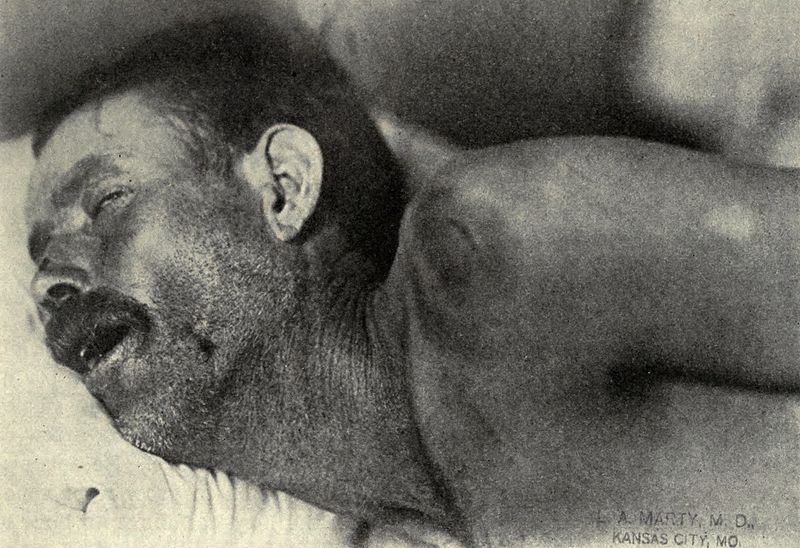

Symptoms of meningitis include:

- Headache

- Nuchal rigidity

- Fever

- Photophobia

- Vomiting

- Altered mental state